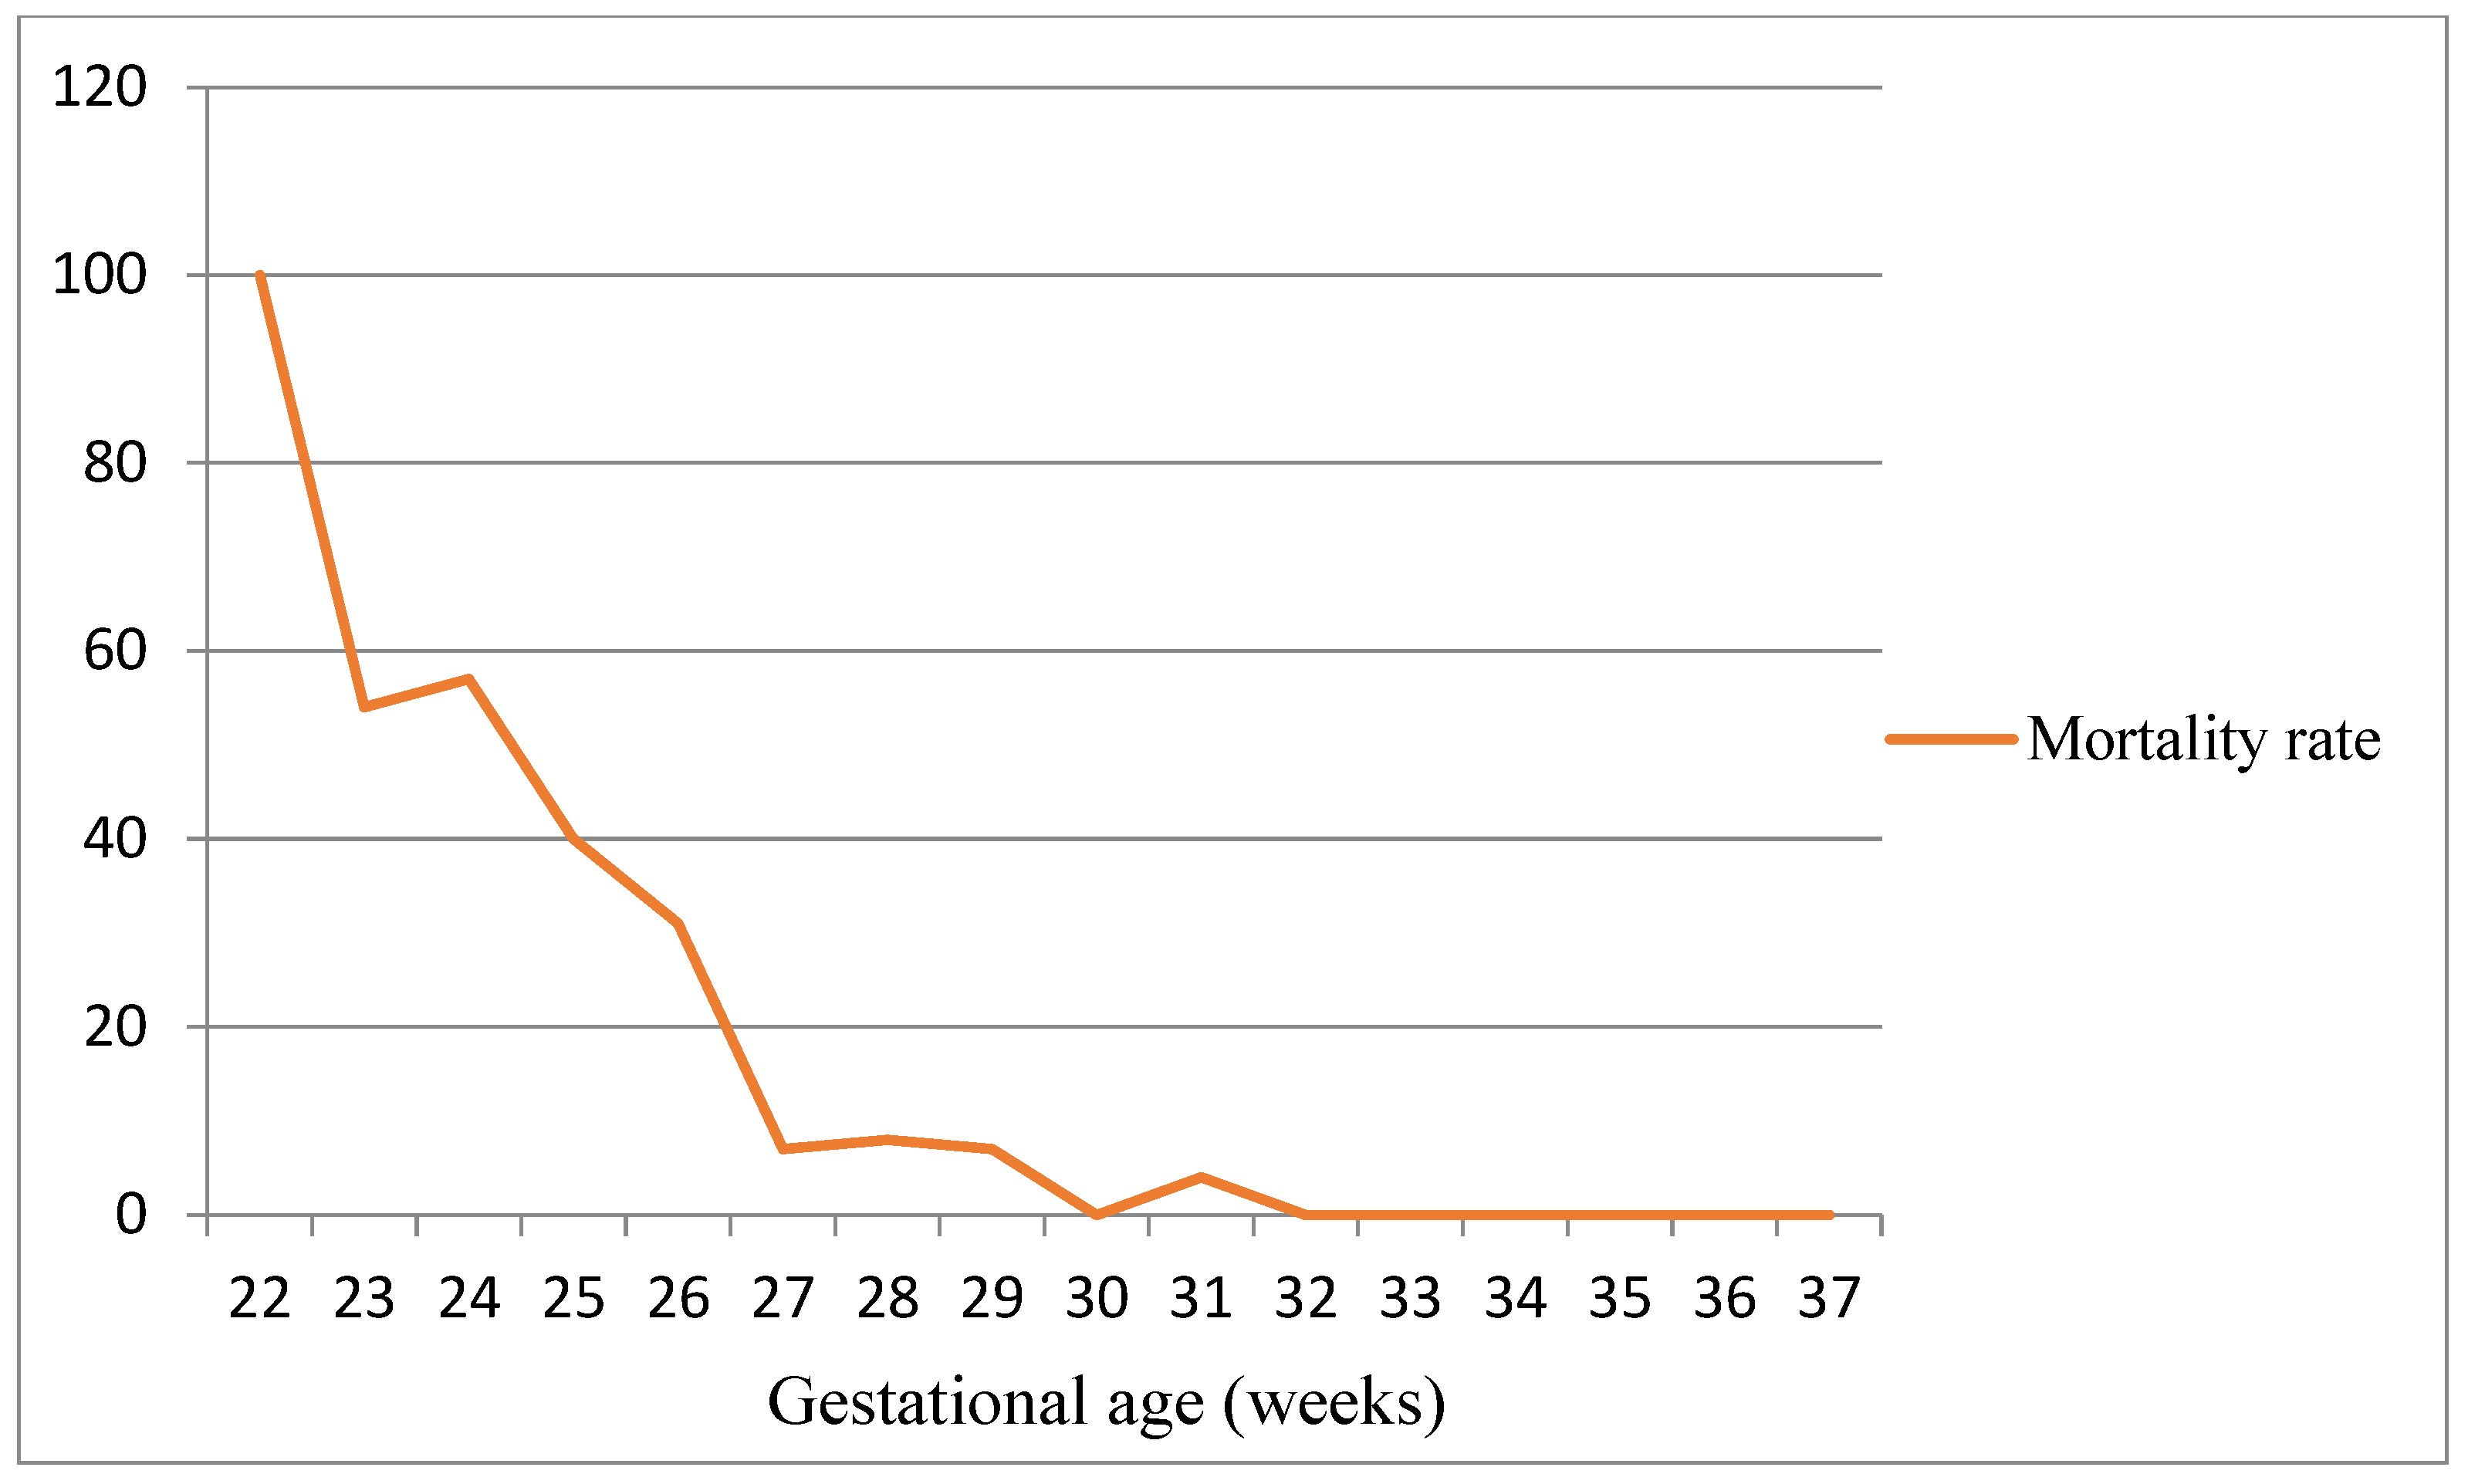

- Stoll, B.J.; Hansen, N.I.; Bell, E.F.; Walsh, M.C.; Carlo, W.A.; Shankaran, S.; Laptook, A.R.; Sánchez, P.J.; Van Meurs, K.P.; Wyckoff, M.; et al. Eunice Kennedy Shriver National Institute of Child Health and Human Development Neonatal Research Network. Trends in Care Practices, Morbidity, and Mortality of Extremely Preterm Neonates, 1993–2012. JAMA 2015, 314, 1039–1051. [Google Scholar] [CrossRef]

- Bell, E.F.; Hintz, S.R.; Hansen, N.I.; Bann, C.M.; Wyckoff, M.H.; DeMauro, S.B.; Walsh, M.C.; Vohr, B.R.; Stoll, B.J.; Carlo, W.A.; et al. Eunice Kennedy Shriver National Institute of Child Health and Human Development Neonatal Research Network. Mortality, In-Hospital Morbidity, Care Practices, and 2-Year Outcomes for Extremely Preterm Infants in the US, 2013–2018. JAMA 2022, 327, 248–263. [Google Scholar] [CrossRef]